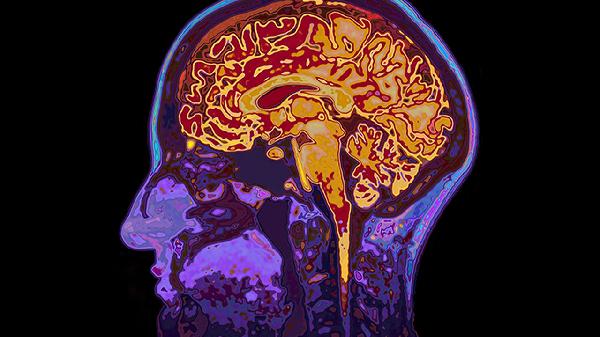

腦血栓形成的原因

腦血栓形成的原因主要有血管內(nèi)皮損傷、血液成分改變、血流動力學異常、動脈粥樣硬化、心臟疾病等。腦血栓通常表現(xiàn)為肢體無力、言語不清、頭暈等癥狀,需及時就醫(yī)干預。